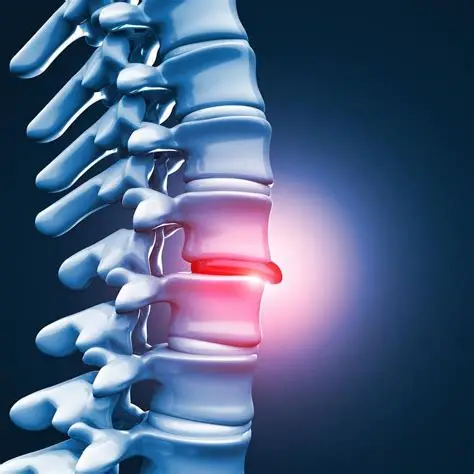

Lumbar Spondylosis

Herniated Disk Or Slipped Disc

Disc Bulge

Cauda Equina Syndrome

Retrolisthesis

Sciatica

Spinal Stenosis

Degenerative Disc Disease

Spondylolisthesis

Ankylosing Spondylitis

Discectomy

Laminectomy

Spinal Fusion